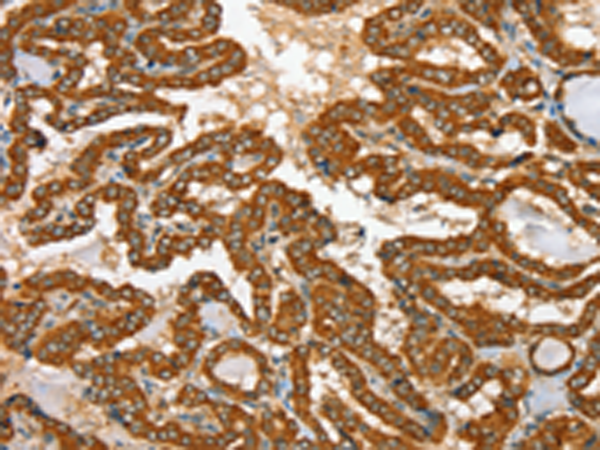

分类: 科研抗体货号: P01689别名: CATX-8; RAB11C应用: IHC反应种属: Human, Mouse